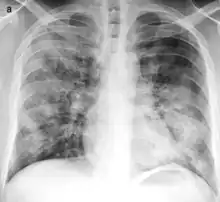

| Typical distribution of lobar pneumonia (left in image) and bronchopneumonia (right in image) | |